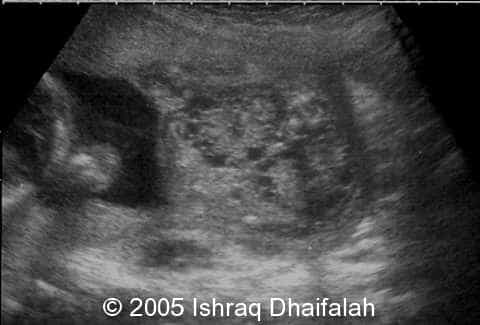

Transverse and longitudinal sections demonstrating the hyperechoic and polycystic kidneys in fetus B:

image5